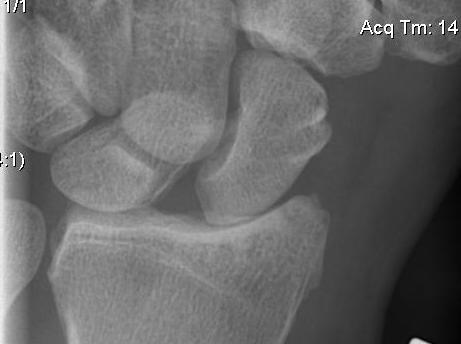

X-ray

Look for signs of SLAC wrist

- degenerative changes of scaphoid fossa with relative sparing lunate fossa

- indicates long standing

AP

Terry Thomas sign

- increased scapholunate interval

- > 3 mm compared with other side

Cortical Ring sign

- end-on view of cortex of distal pole of scaphoid

Scaphoid shortened

- due to palmar flexion

Lateral

Palmarflexion of scaphoid

Dorsiflexion of lunate

Increased scapholunate angle

- > 70o

- usually 30 - 60o

Increased luno-capitate angle

- normally < 10o

Increased radio-lunate angle

- lunate extended > 10o